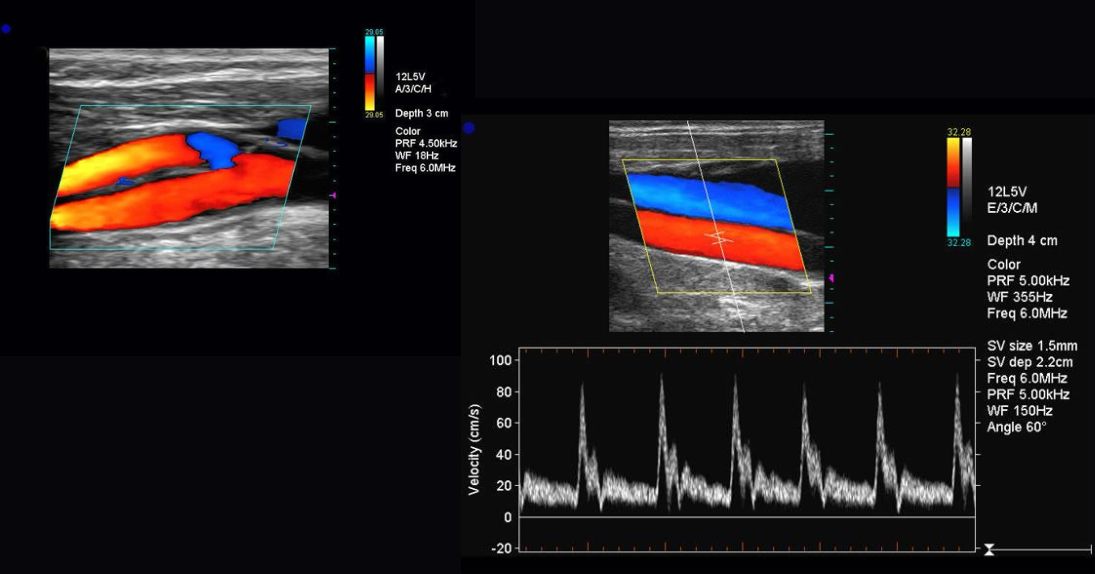

Doppler Color

Estudios vasculares avanzados.

• Doppler vasculares

• Doppler renales

• Doppler tiroides